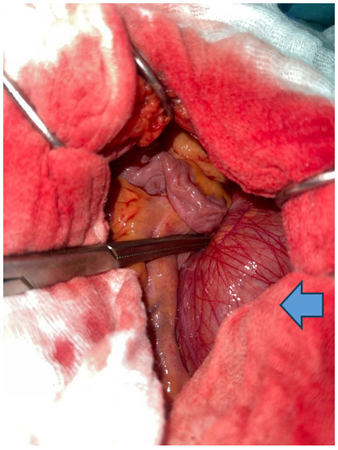

Careful reduction of the hernia contents was achieved, consisting of approximately 2.30 meters of viable small bowel. The hernia defect was closed using absorbable sutures.

Figure 3: Intraoperative view before reduction of the hernia contents.